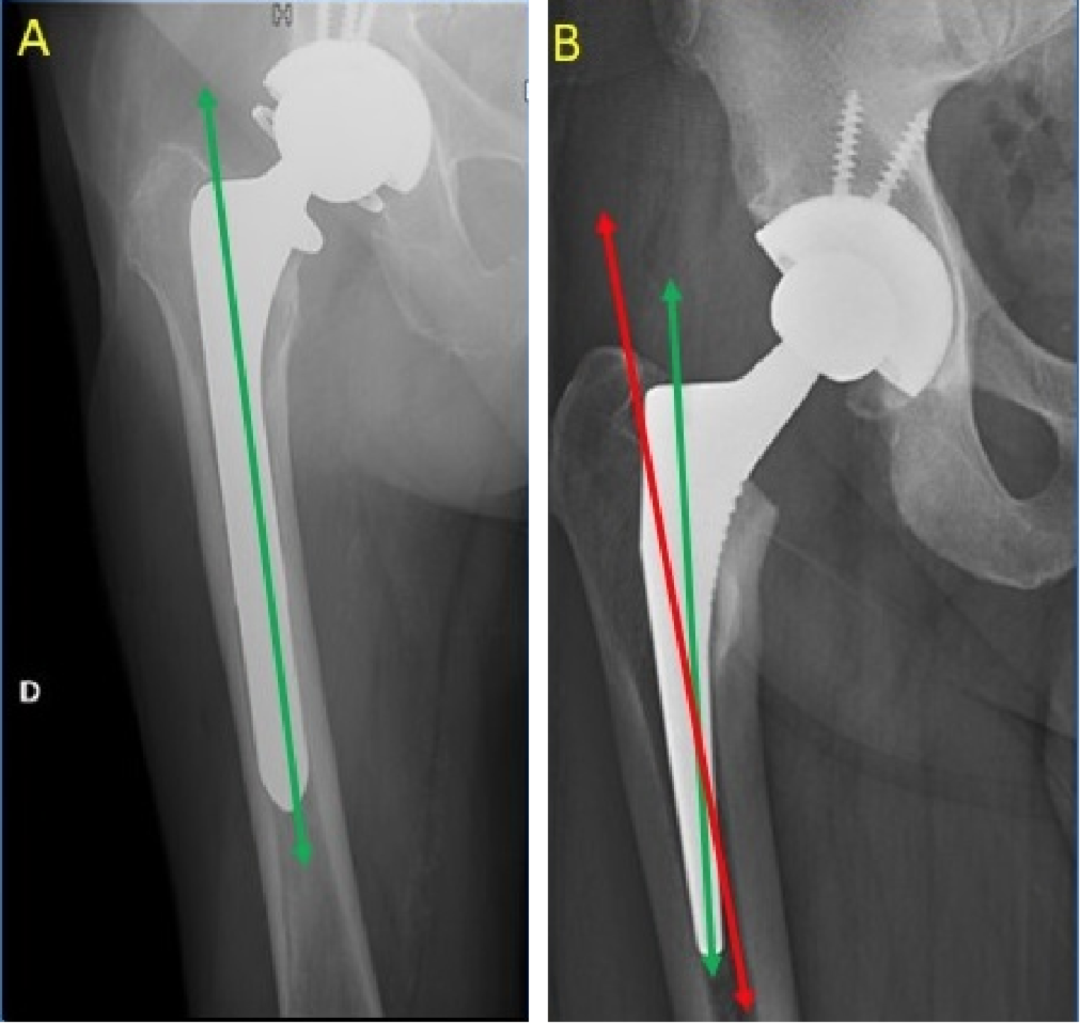

④股骨假体的位置:

正位 X 线片上测量假体柄长轴与股骨长轴间角度来确定,夹角≤3°为中心固定,超出为内翻或外翻固定。股骨假体内翻容易造成假体松动。

⑤股骨柄定位:

股骨柄(红线)与股骨颈纵轴(绿线)的位置比较。正常 5°~10°。